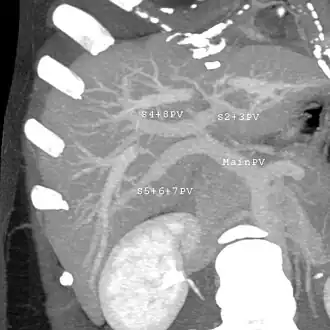

Couinaud classification system

In the widely used Couinaud system, the functional lobes are further divided into a total of eight subsegments based on a transverse plane through the bifurcation of the main portal vein.[30] The caudate lobe is a separate structure that receives blood flow from both the right- and left-sided vascular branches.[31][32] The Couinaud classification divides the liver into eight functionally independent liver segments. Each segment has its own vascular inflow, outflow and biliary drainage. In the centre of each segment are branches of the portal vein, hepatic artery, and bile duct. In the periphery of each segment is vascular outflow through the hepatic veins.[33] The classification system uses the vascular supply in the liver to separate the functional units (numbered I to VIII) with unit 1, the caudate lobe, receiving its supply from both the right and the left branches of the portal vein. It contains one or more hepatic veins which drain directly into the inferior vena cava.[30] The remainder of the units (II to VIII) are numbered in a clockwise fashion:[33]

With the recent advances of noninvasive imaging, living liver donors usually have to undergo imaging examinations for liver anatomy to decide if the anatomy is feasible for donation. The evaluation is usually performed by multidetector row computed tomography (MDCT) and magnetic resonance imaging (MRI). MDCT is good in vascular anatomy and volumetry. MRI is used for biliary tree anatomy. Donors with very unusual vascular anatomy, which makes them unsuitable for donation, could be screened out to avoid unnecessary operations.

MDCT image. Portal venous anatomy contraindicated for liver donation -

MDCT image. 3D image created by MDCT can clearly visualize the liver, measure the liver volume, and plan the dissection plane to facilitate the liver transplantation procedure. -